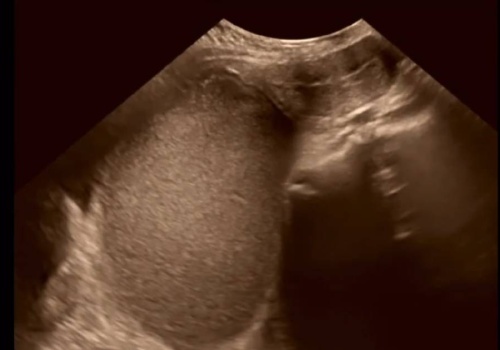

Do gabinetu ginekologicznego zgłosiła się 14-letnia dziewczyna, która nie miała jeszcze pierwszej miesiączki. Lekarz dość szybko zdiagnozował problem, choć, jak się okazuje, taka przypadłość zdarza się niezwykle rzadko. Okazało się, że przyczyną braku pierwszego okresu u nastolatki była zarośnięta b...